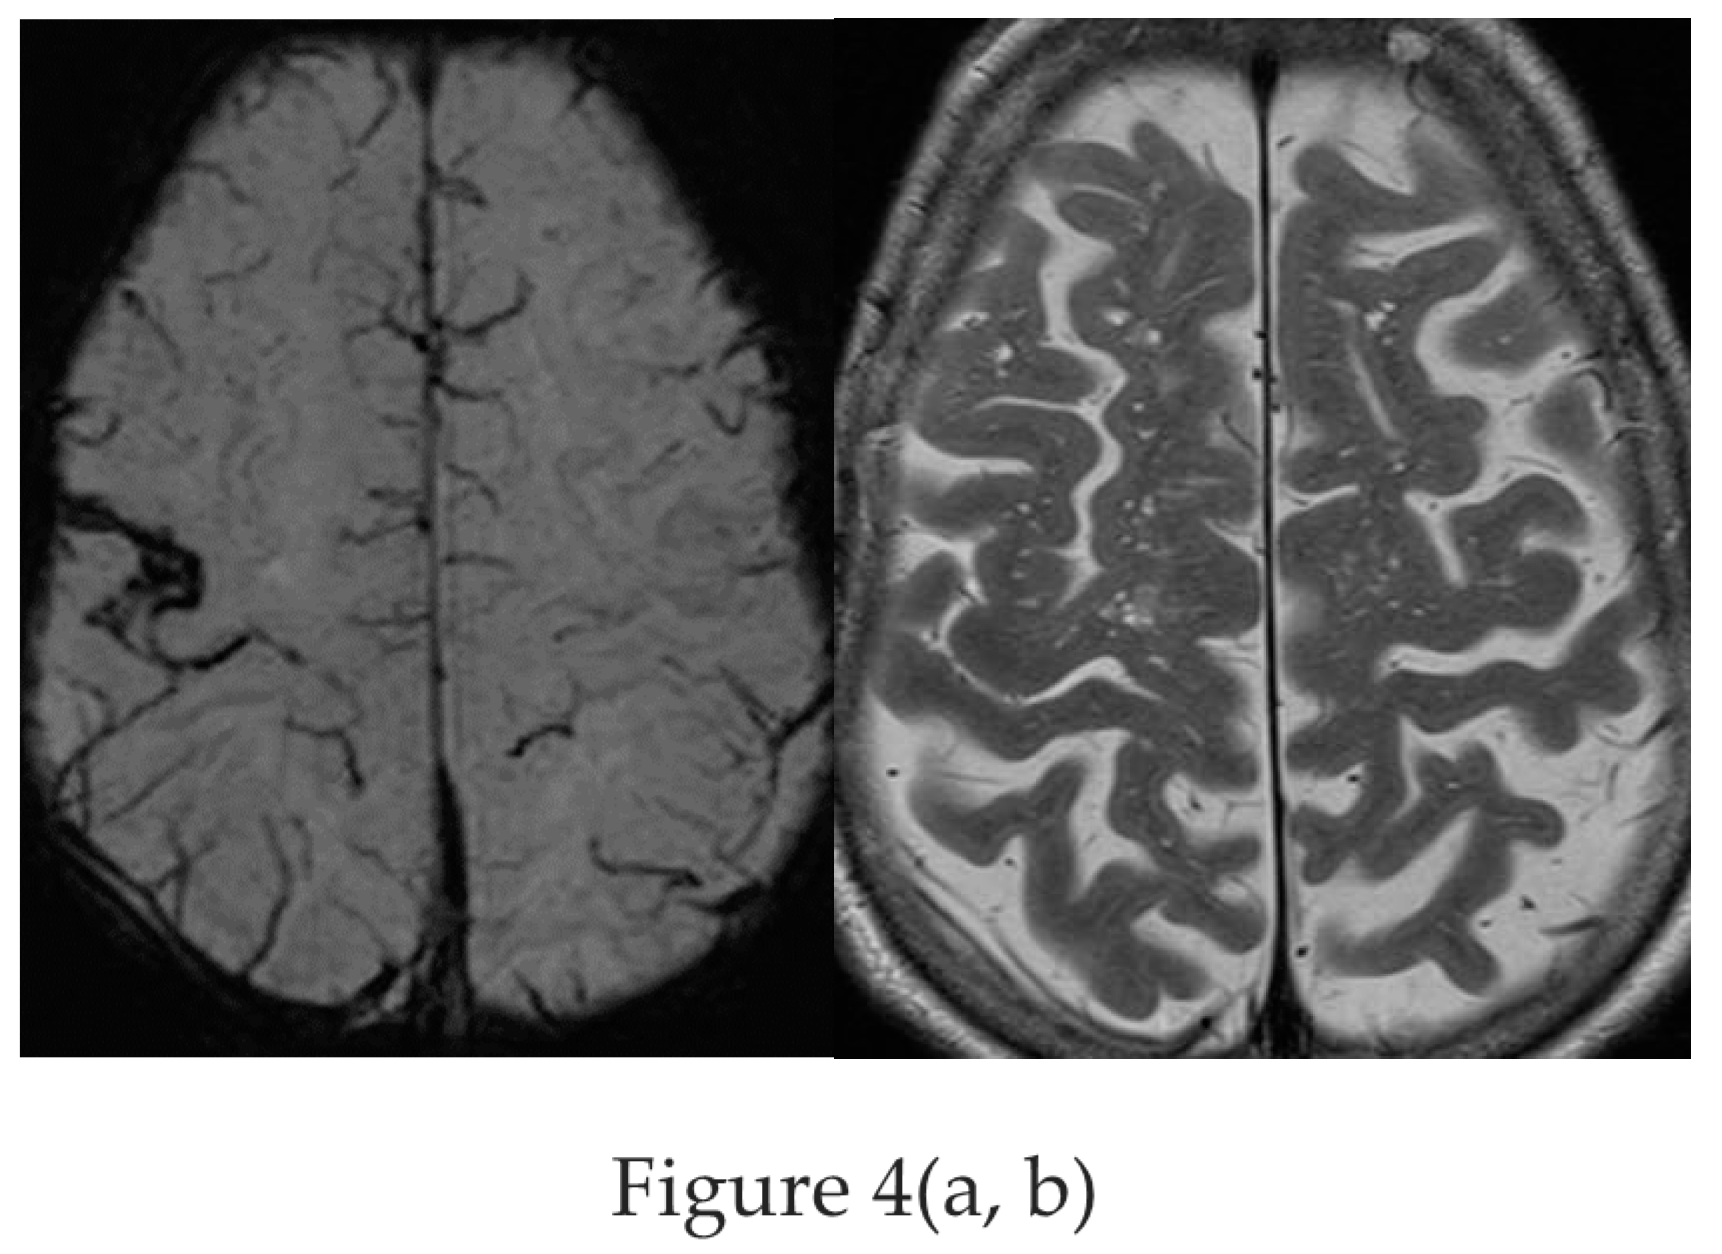

4.5. New MR Sequences Display Tissue Properties for Improved Visualization of Lesions

4.6. Postprocessing by Morphometric Analysis Improves Focal Lesion Detection Beyond Visual Analysis

4.7. Postprocessing by Quantitative Analysis of Signal Intensity, Volumetry Enhances Temporal Lesion Identification

4.8. Postprocessing by 3D Surface Rendering Technique to Improve Comprehension of Superficially Located Lesions

4.9. MR Fingerprinting Exploits Tissue Properties to Reflect “Activity“ of a Lesion

4.10. MR Perfusion Exploits Blood Flow to Identify Interictal Laterality of a Focus

4.11. Contrast Administration Is of Limited Gain with Respect to Lesion Detection But May Contribute to Characterization of an Abnormality